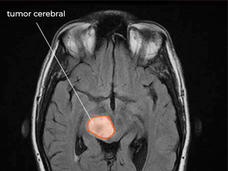

Estudio de glioblastoma destaca las diferencias de sexo en el cáncer de cerebro

Hombres y mujeres con glioblastoma parecen responder en forma diferente a tratamiento convencional. Un nuevo estudio identifica factores biológicos que pueden contribuir a esta diferencia de sexo.

Prueba de sangre se muestra prometedor para detectar cambios genéticos en tumores cerebrales

Un análisis de sangre de biopsia líquida puede detectar el ADN de tumores cerebrales llamados gliomas difusos de línea media, han descubierto los investigadores. Esta prueba de mínima agresividad podría usarse para identificar y rastrear cambios moleculares en niños con estos tumores cerebrales altamente mortales.